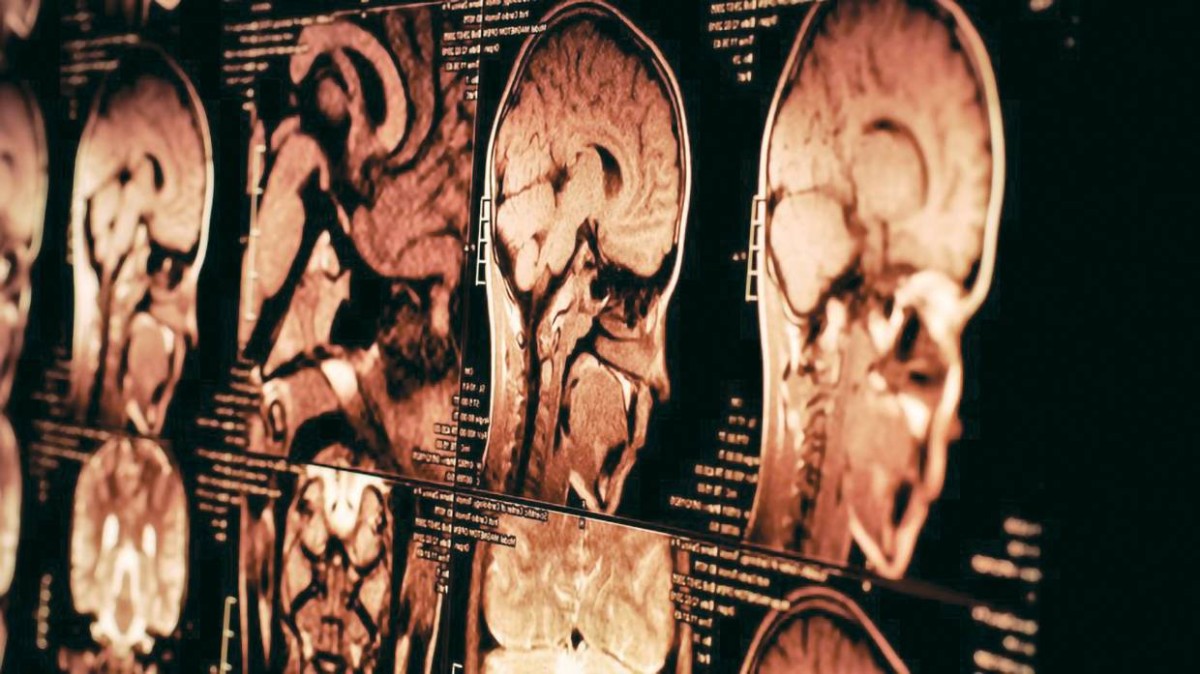

كان يُعتقد أن جيناً واحداً، يُسمى FOXR2 نشط فقط في نوع نادر من أورام الدماغ لدى الأطفال، لكنّ بحثاً جديداً من مستشفى سانت جود لأبحاث الأطفال يُظهر أن هذا الجين يمكن أن يكون نشطاً بالفعل في أنواع مختلفة من أورام الدماغ لدى الأطفال منها 31 ورماً عدوانياً، وليس فقط ورم الأرومة العصبية.

جين متورط في 31 ورماً